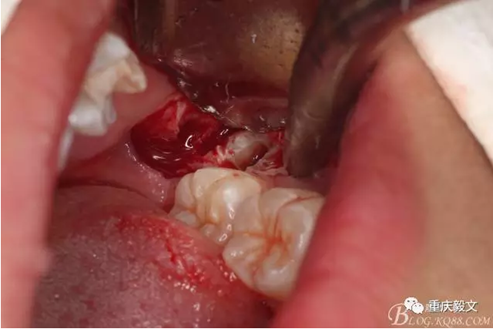

圖2 口內(nèi)像,38牙冠未萌出,可探及38牙冠。從此可以結(jié)合x光片,判斷38位地位近中埋伏阻生。這樣就確定我們的拔牙手術(shù)方案:切開+翻瓣+去骨+分牙的手術(shù)步驟。

圖5切開、翻瓣、去骨、暴露38牙冠。翻瓣從兩個切口的交接處開始。掀起的瓣是全厚瓣。